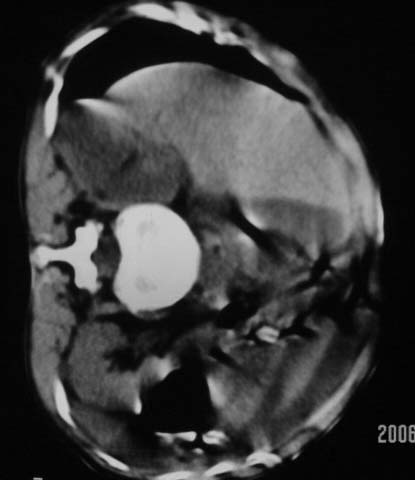

仰卧位见:肝前间隙及肝脾间隙内可见新月形气体密度影,边缘清楚,侧卧位见气体随体位改变而移动,ct值约-929hu。膈下、肝下间隙及部分肠间隙可见液性密度影。考虑:1、上腹部空腔脏器穿孔,以胃穿孔可能性大。2、少量腹水。

仰卧位见:肝前间隙及肝脾间隙内可见新月形气体密度影,边缘清楚,侧卧位见气体随体位改变而移动,ct值约-929hu。膈下、肝下间隙及部分肠间隙可见液性密度影。考虑:1、上腹部空腔脏器穿孔,结合临床,首先考虑胃穿孔可能性大。2、少量腹水

支持消化道空腔脏器穿孔(腹腔内大量游离气体影,小网膜囊内亦见气体影),少量腹水。

可见游离气体,上消化道穿孔,少量腹水,腹膜炎